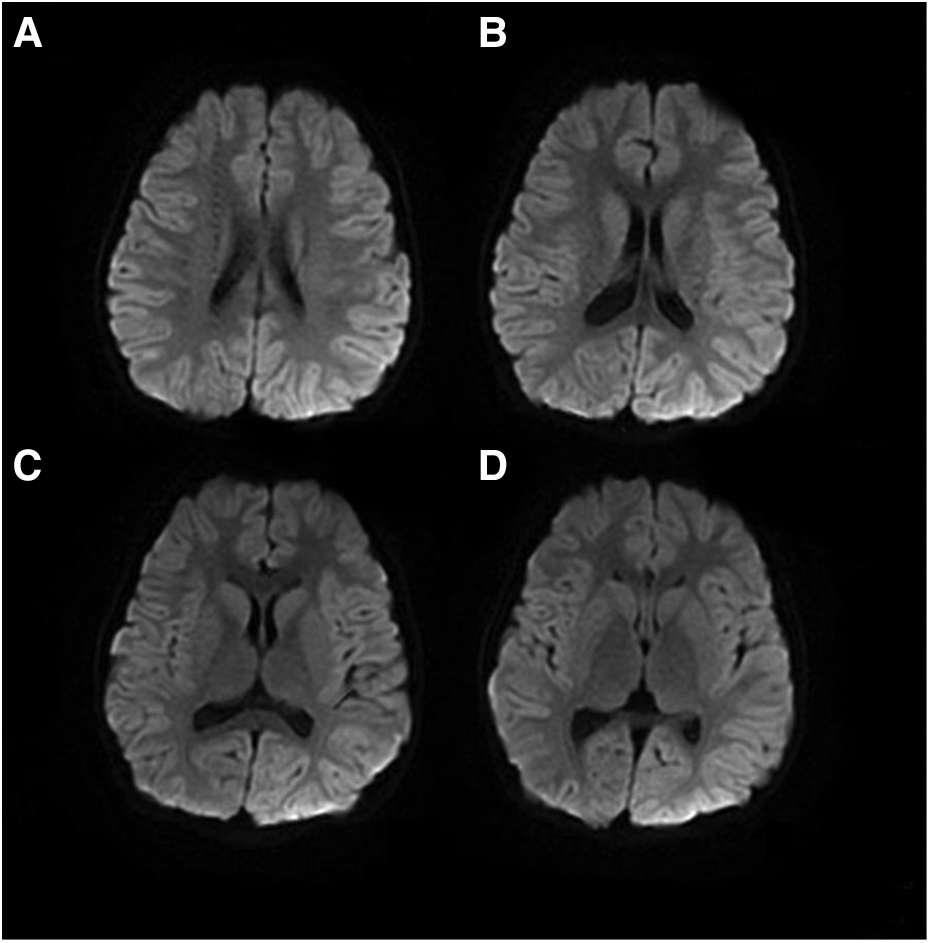

The patient was finally diagnosed with hemiplegic migraine presenting as an acute encephalopathy. He was given daily flunarizine 3 mg (0.2 mg/kg) to prevent HM attacks. After treatment for 1.5 months, a follow-up MRI showed complete disappearance of abnormal signals throughout the right hemispheric cortex (Figure 6). The video EEG was not reviewed because the patient fully recovered to the pre-onset level and the patient's compliance was not high.

Figure 6

The brain MRI of Patient #1 showed complete disappearance of abnormal signals 1.5 months after treatment (A–D).